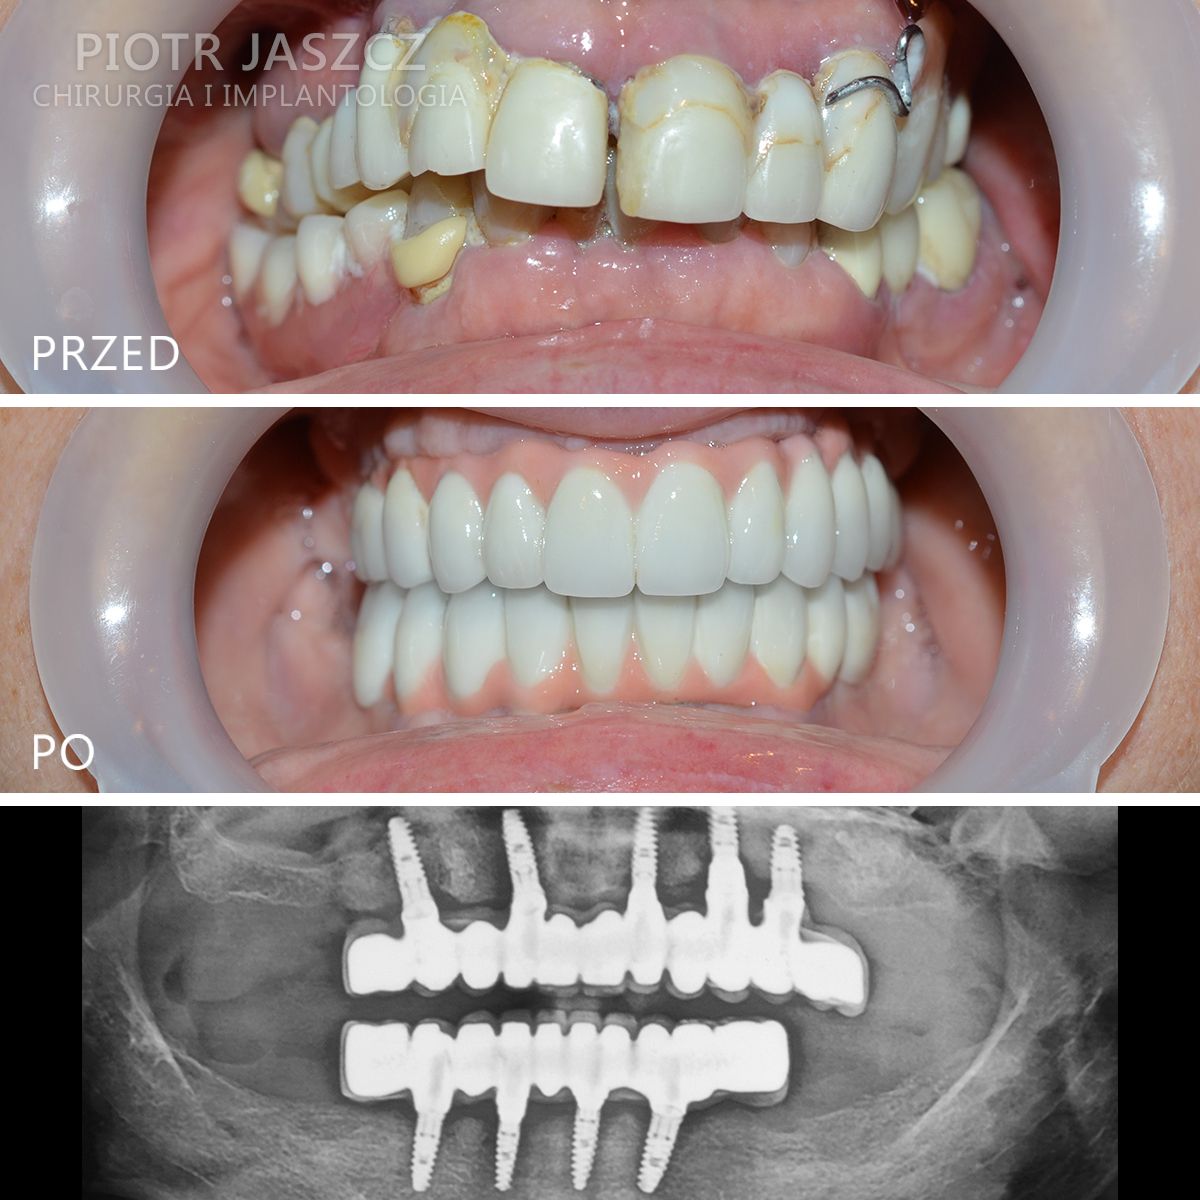

Specjalizuje się głównie w skomplikowanych odbudowach implantologicznych pacjentów bezzębnych oraz w zaawansowanych regeneracjach kostnych w leczeniu implantologicznym metodami przeszczepów kości własnej, jak również w przeszczepach tkanek miękkich w celu regeneracji dziąsła przy zębach lub przy implantach.

Wykonuje zabiegi odtworzenia zębów w 24h, polegające na usunięciu wszystkich zębów w szczęce lub żuchwie, wszczepieniu implantów metodą All-on-4 lub All-on-6 oraz oddaniu mostów na wszczepionych implantach w 24h. Metamorfozy szczęki w 24h.